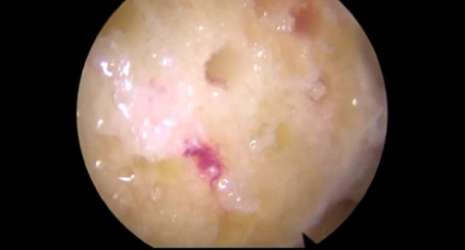

자가연골이식술 (OATS)

체중 부하를 받지 않는 부위의 건강한 연골을 손상된 연골에 이식하는 방법입니다.

미세천공술을 시행하기에는 손상 부위가 크고, 인공관절 수술을 하기엔 손상 부위가 작은 경우 주로 시행됩니다.

자가연골이식술은 뼈와 연골을 함께 채취하여 손상된 부위에 이식하므로 흡착력이 높아 연골재생이 빠르며 통증이 적고 회복 기간이 짧습니다.

① 관절경으로 손상된 부위를 확인한 후 크기를 측정합니다.

② 체중 부하가 되지 않는 부위의 무릎 연골을 뼈와 함께 손상 부위 크기만큼 채취합니다.

③ 손상된 연골 부위로 이식합니다.